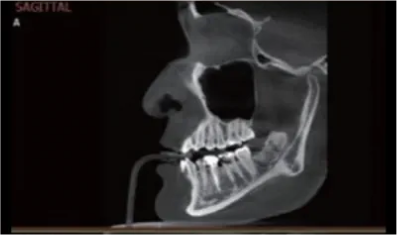

Zdobędziesz pogłębioną wiedzę na temat anatomii jamy ustnej, ze szczególnym uwzględnieniem obszarów wymagających rekonstrukcji kostnej.

Poznasz szerokie spektrum zastosowań klinicznych implantów MaiImplants, w tym w przypadkach znacznej atrofii kości. Zobaczysz przykłady udanych zabiegów i dowiesz się, jak uniknąć potencjalnych powikłań.

Szczegółowo omówimy każdy etap procedury implantacji, od przygotowania pacjenta po opiekę pozabiegową. Poznasz tajniki pracy z implantami MaiImplants, co pozwoli Ci uniknąć błędów i zapewnić pacjentom bezpieczeństwo i komfort podczas zabiegu.